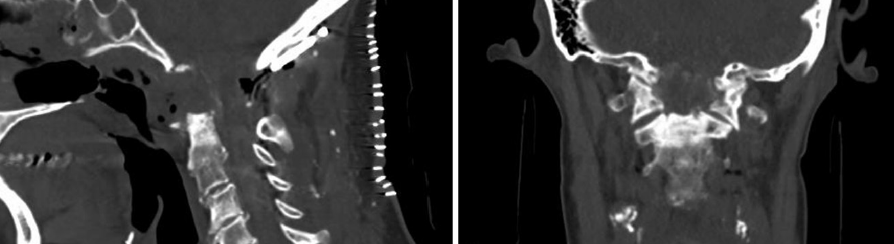

A 67-year old woman with chronic hypertension, hyperlipidemia and diabetes mellitus non-compliant to medication presented with a 10-day history of recurrent visual phenomena in the left visual field. She described stationery multi-coloured flashing lights which decreased in intensity, brightness and size after 3 minutes. She was alert and conscious during attacks. There was no limb jerking. Neurological examination was normal with no visual field defect. Capillary glucose was 28.1 mmol/L, Hba1c 9% and B-hydroxybutyrate < 0.1. She was treated with actrapid 8 units, glipizide 5 mg BD and empagliflozin 12.5 mg OM. Interictal electroencephalogram was normal with no epileptiform activity. Brain magnetic resonance imaging revealed restricted diffusion in the right occipital cortex with corresponding cortical thickening and increased FLAIR signal with subtle hypodensity on GRE sequence. Her visual symptoms improved dramatically with hydration and diabetic control. She was treated with a short course of keppra. One month later repeat MRI brain showed resolution of the DWI and FLAIR abnormalities.

Initial dwi

D